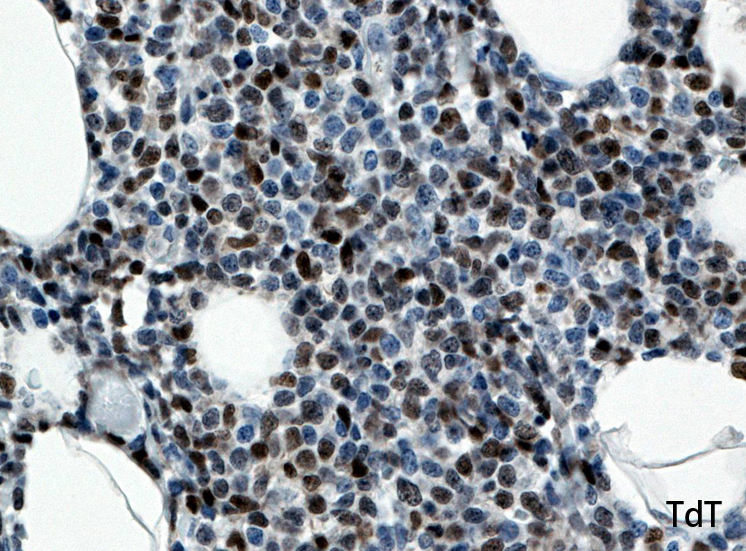

皮膚生検組織病理所見

真皮, 毛嚢周囲, 皮下組織にびまん性または結節様に異型細胞の浸潤増殖が認められる(Fig.05)。表皮への浸潤は認められない。真皮上層への浸潤細胞は類円形,多角形のhyperchromatic nucleiをもつ。細胞質は明るくclearに見える(Fig.06)。毛嚢周囲に浸潤する細胞はリンパ節への浸潤細胞と同様の形態を示す(Fig.7). 腫瘍細胞はCD123陽性を示した(Fig.9)